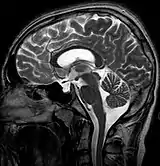

| MRI of Empty Sella | |

Empty sella syndrome is the condition when the pituitary gland shrinks or becomes flattened, filling the sella turcica with cerebrospinal fluid instead of the normal pituitary.[2] It can be discovered as part of the diagnostic workup of pituitary disorders, or as an incidental finding when imaging the brain.[1]

| Diagnostic method | MRI, CT scan[1] |